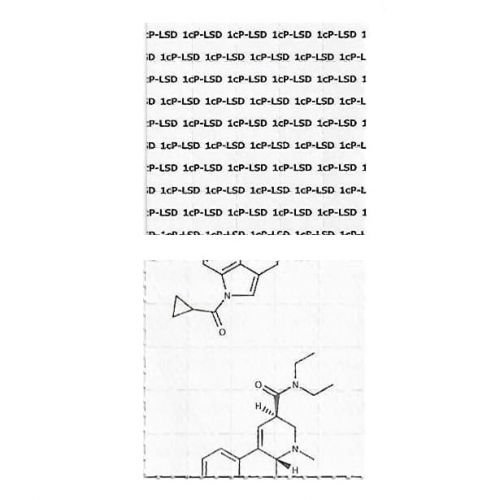

1cP-LSD Blotters – 100mcg

Price range: € 23.75 through € 299.00

1cP-LSD Micro Blotters – 20mcg

Price range: € 31.25 through € 95.00